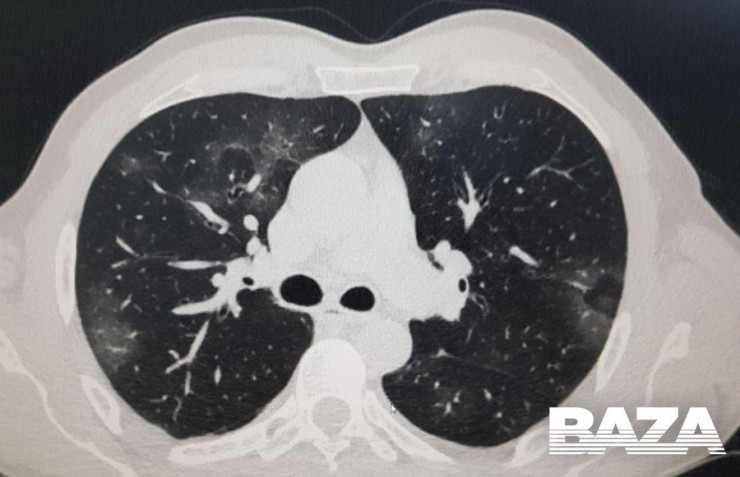

Одна из отличительных особенностей вирусной пневмонии - это симметричное поражение легких с полисегментарными воспалительными изменениями (в нескольких частях, то есть в разных долях и разных не смежных сегментах). Другие виды пневмонии развиваются, как правило, в пределах одной доли легкого, а не везде. Так, при заболевании COVID-19 на компьютерных томограммах видны уплотнения легочной ткани, похожие на прозрачные потертые пятна. В медицине такие патологии называют симптомом "матового стекла".

На ранней стадии развития вирусной пневмонии (проявляется до четвертого дня заболевания) "матовое стекло" возникает не более чем в трех очагах. При этом уплотнения распространяются преимущественно в нижних долях и по периферии, а их максимальный диаметр не превышает три сантиметра. Из-за повреждений в альвеолах скапливается жидкость, которая приводит к нарушению кислородного обмена и кислородному голоданию пациента, такие пациенты начинают жаловаться на одышку и затрудненность дыхания.

Затем пневмония начинает прогрессировать. В течение пяти-восьми дней количество уплотнений по типу "матового стекла" становится больше, и они постепенно трансформируются в очаги консолидации по периферии легких.